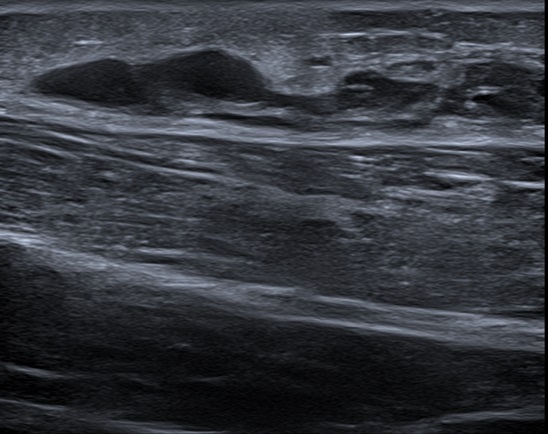

Ante estos hallazgos, se solicitó una radiografía de extremidad inferior izquierda (Fig. 1), en la que se observó un aumento de partes blandas y se descartó patología ósea.

| Figura 1. Radiografía de extremidad inferior izquierda en la que se observa aumento de partes blandas sin patología ósea |